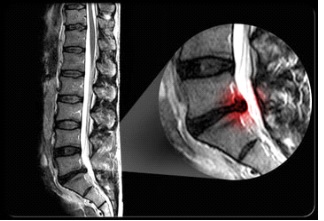

La diagnosi avviene in seguito a visita specialistica neurochirurgica volta ad accertare che la sintomatologia riferita dal paziente sia congrua con le immagini radiologiche. Il principale esame da valutare prima di porre un’eventuale indicazione chirurgica è la risonanza magnetica lombo-sacrale che è l’esame più specifico per mettere in risalto le caratteristiche del disco vertebrale. A completamento diagnostico può essere consigliata l’esecuzione di TC lombo-sacrale, per mettere meglio in risalto il profilo osseo delle vertebre sovra- e sottostanti, e una elettromiografia per evidenziare eventuali segni di sofferenza radicolare.